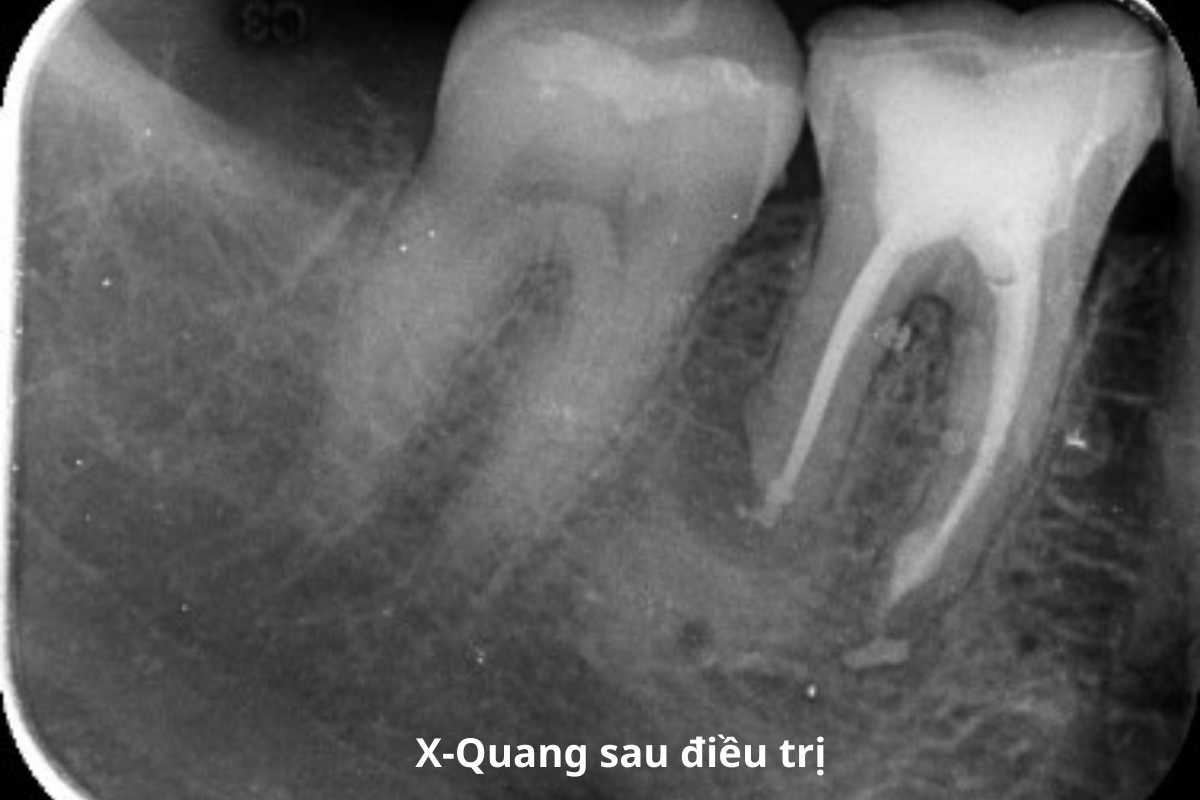

- Kế hoạch: điều trị nội nha lại răng 46, nhổ răng khôn mọc lệch và trám các răng sâu.

BEFORE & AFTER